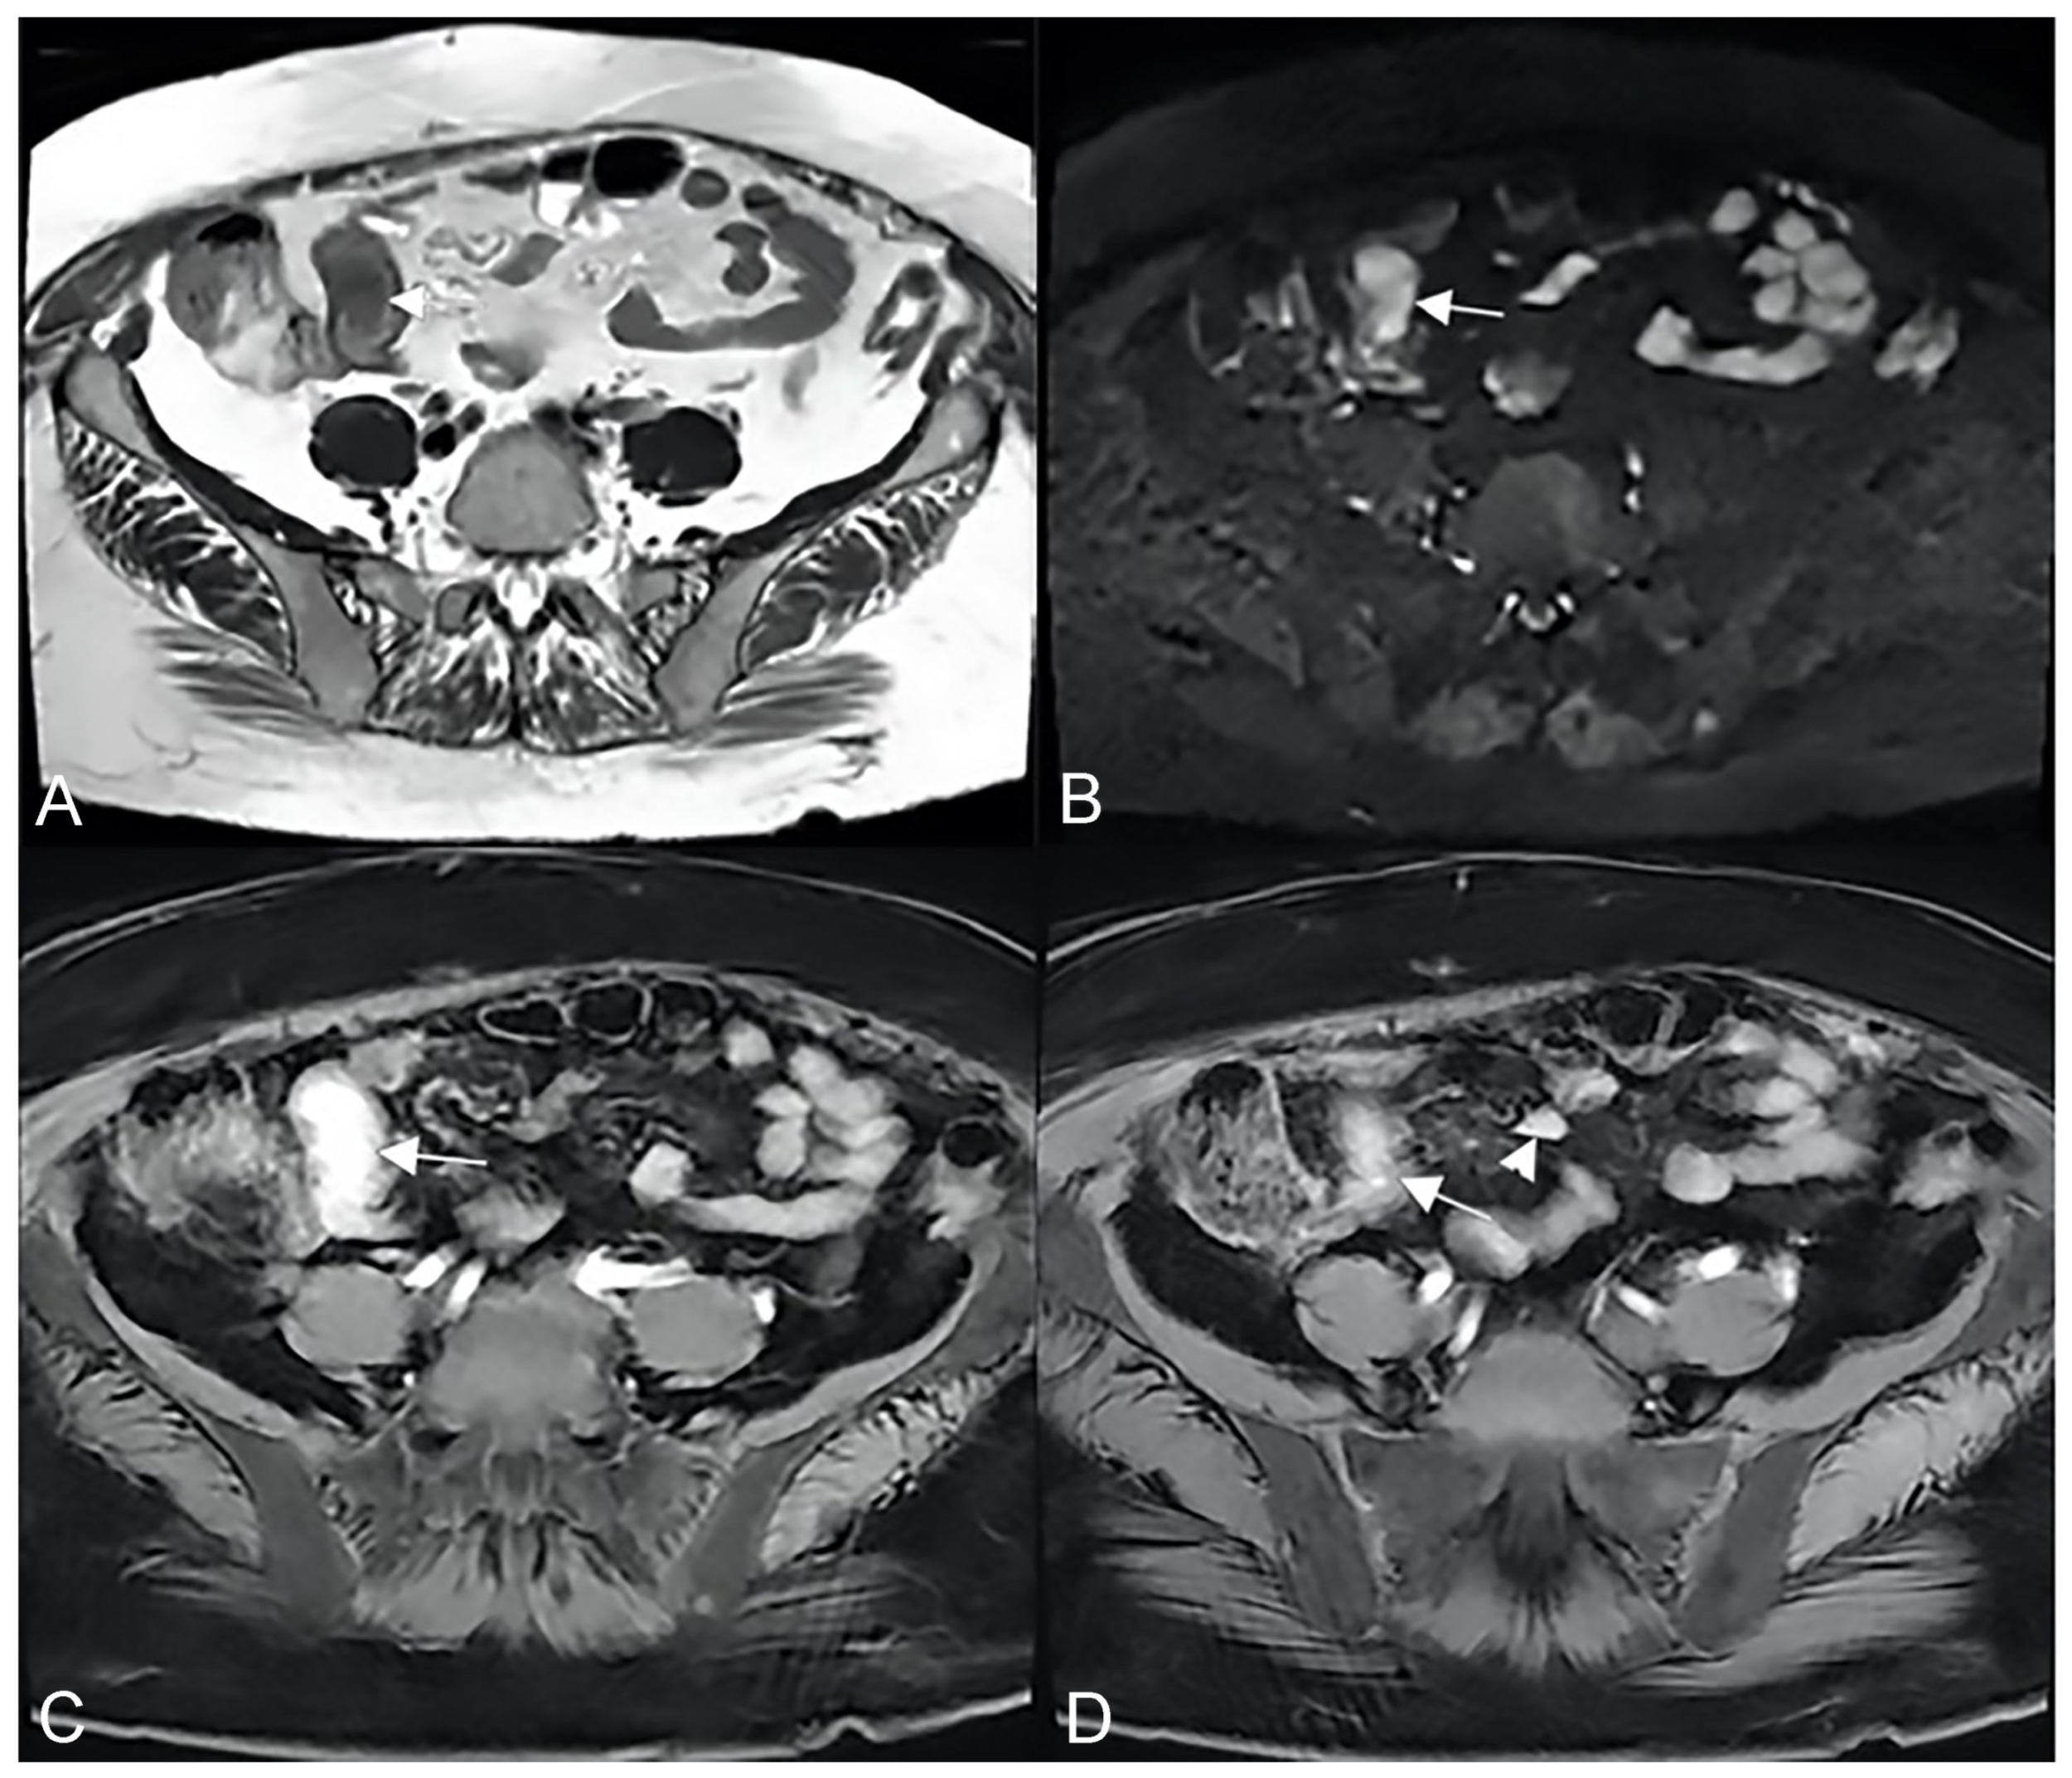

Unlike the sinus tracts, a fistula is defined as a pathologic channel connecting two or more epithelialized surfaces [11]. Fistulae can be simple (single extra enteric tract: enter enteric, enter colic, enter vesical, enterocutaneous, or rectovaginal) or complex (branching and intersecting fistulas, sometimes with a star-like appearance [5]). They represent a complication in approximately 14–50% of the patients with Crohn’s disease (Figure 9, Figure 10 and Figure 11).

Figure 9.

Pathological junctions of intestinal segments through enteroenteric fistulas, which represents internal fistulas that connect intestinal segments such as ileo-sigmoidal (A) and ileo-colic (B).